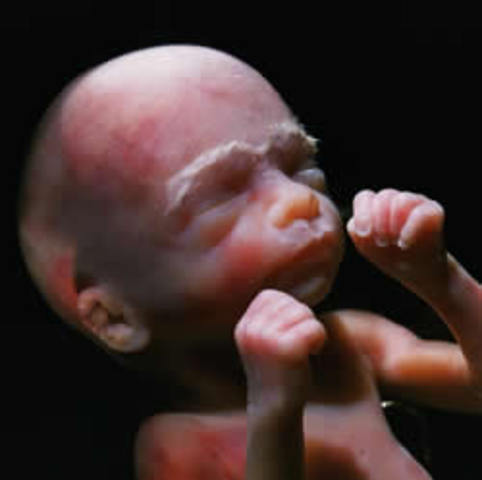

• week 29 of the fetal development

week 29 of the fetal development

The bones are fully developed but soft. The fettus can suck his thumb.